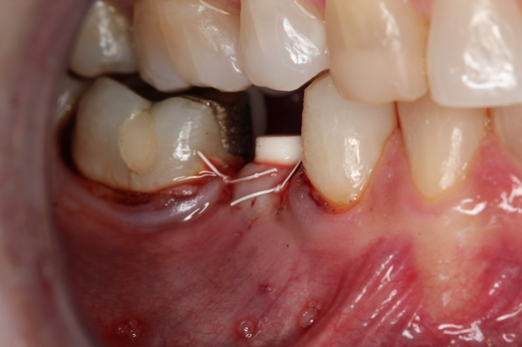

Fig 20. Immediately after extraction and placement.

Figure 20

Fig 21. Retainer provisional.

Figure 21

Occasionally dentists are presented with extreme challenges with long-term restorations and replacing missing teeth. Dentists must evaluate the patient's condition, develop optimum long-term oral health, and attempt to meet the patient's expectations. Figure 18 showed a class III malocclusion with deep bite, multiple abfractions, and less-than-ideal occlusal plane, but the patient wanted to replace his maxillary right canine only. A discussion with the patient regarding occlusal disharmonies and comprehensive recommendations for full-mouth rehabilitation revealed that the patient had a limited budget for dental care. The patient understood the ramifications of his comprehensive dental needs not being affordable. Decisions were made to atraumatically remove the maxillary right canine (Figure 19) and immediately place a ceramic dental implant (Figure 20). Polytetrafluoroethylene (PTFE) 4-0 sutures were placed to help support soft tissues, and then a full-arch Essix-style retainer with a flowable composite facial veneer was used to provide some esthetics during the patient's healing phase (Figure 21). The implant and the retainer were not to be in contactthe retainer may occlude with the opposing dentition and also be passive in relation to the ceramic implant.